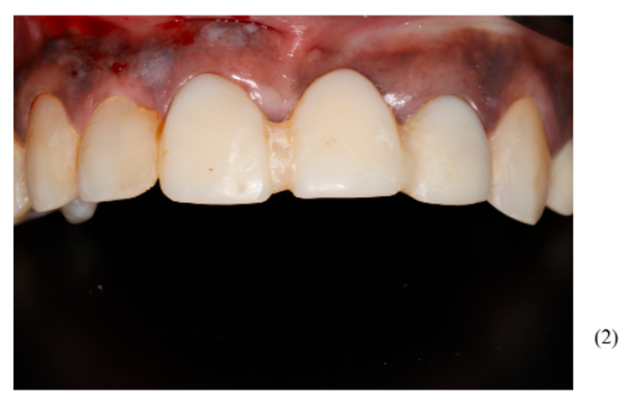

Figuras 1 e 2 – Visão intrabucal da paciente, evidenciando instabilidade da prótese fixa de resina, bem como sua deficiência estética.

A reabilitação final ocorreu após um ano do início do tratamento cirúrgico da enxertia óssea. Foram confeccionados provisórios para preparo do perfil gengival, visando uma ótima estética rosa.

Utilizamos três munhões do tipo Ideale – Implacil De Bortoli de altura 3.3×2.5×4 mm para confecção das próteses do tipo parafusada (imagens 10 e 11). A foto final foi no acompanhamento de seis meses, onde podemos observar ótima estabilidade do tecido peri-implantar (imagem 12).